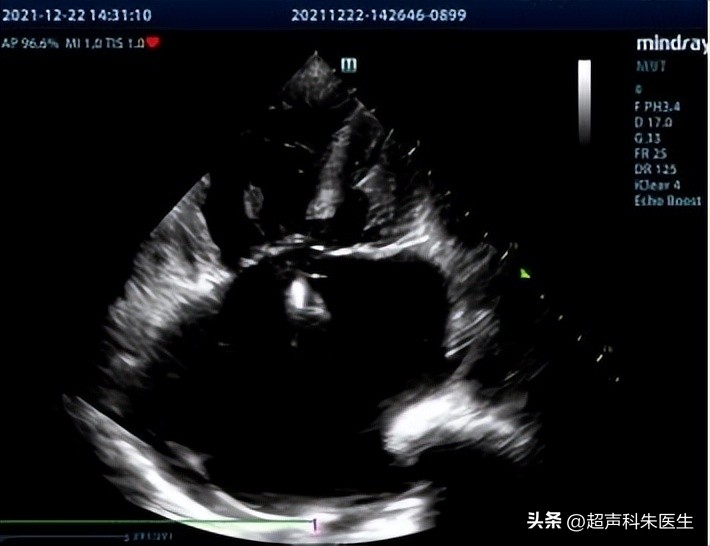

首选 超声 检查,直接征象:房间隔或冠状静脉窦顶盖的回声失落和房水平分流。

间接征象:1.右心增大。

3.右室负荷增加,或出现室间隔与左室后壁同向运动。